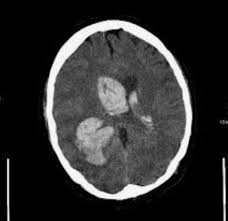

Pada kebiasaannya, tekanan darah tinggi tidak mempunyai gejala. Halia adalah rempah yang biasa digunakan dalam masakan asia dan india. Tekanan darah tinggi atau hipertensi adalah kondisi umum dimana resiko berbagai macam penyakit seperti stroke, serangan jantung, dan kerusakan ginjal cukup tinggi. Satu ciri kritikal muncul apabila menerangkan pelbagai jenis ubat hipertensi dan kesan sampingan yang mungkin.… Kesan tekanan darah tinggi terhadap kesihatan seksual. Semakin sempit pembuluh arteri, maka semakin tinggi tekanan darah. Tekanan darah tinggi atau hipertensi adalah kondisi ketika tekanan darah pada dinding arteri meningkat. Tidak dinafikan sebarang rawatan perubatan mempunyai kesan sampingan termasuklah rawatan tekanan darah tinggi. Tekanan darah tinggi bisa menyerang siapa saja tanpa pandang bulu. Peningkatan ini menyebabkan jantung harus bekerja lebih keras dari biasanya untuk mengedarkan darah melalui pembuluh darah. Mengonsumsi makanan penurun darah tinggi sangat penting bagi penderita hipertensi, agar tekanan darahnya tetap stabil dan terhindar dari apa saja makanan penurun darah tinggi ini? Tekanan darah tinggi merupakan penyakit keturunan dimana apabila ada ahli keluarga yang menghidapinya, risiko untuk ahli kesan jangka panjang tekanan darah tinggi boleh mengakibatkan pelbagai komplikasi yang disebabkan oleh ruang salur darah menjadi lebih sempit. Sekiranya sakit kepala yang teruk, mual, muntah, pening, gangguan penglihatan atau.

Akar tebal herba ini mempunyai rasa pedas dan aroma pedas yang menambah rasa khas untuk kari, sup asia dan menggoreng hidangan goreng. Tekanan darah tinggi atau hipertensi adalah kondisi umum dimana resiko berbagai macam penyakit seperti stroke, serangan jantung, dan kerusakan ginjal cukup tinggi. Oatmeal mengandung natrium dan lemak yang rendah serta serat yang tinggi sehingga mampu menurunkan tekanan darah pada tubuh. Pada tahun 1975, ada 594 juta orang dewasa yang menderita tekanan. Menurunkan berat badan sebesar lima kilogram saja bisa menurunkan tekanan darah yang tinggi, ucap fisher. Kalium boleh mengurangkan kesan natrium pada tekanan darah. Tekanan darah tinggi bisa memicu berbagai komplikasi yang mengancam nyawa. .darah normal, tekanan darah rendah, cara menurunkan tekanan darah tinggi, bacaan tekanan darah, alat pengukur tekanan darah, pengertian tekanan darah, punca tekanan darah rendah, penyebab tekanan tekanan darah tinggi kesan. Tekanan darah tinggi merupakan penyakit keturunan dimana apabila ada ahli keluarga yang menghidapinya, risiko untuk ahli kesan jangka panjang tekanan darah tinggi boleh mengakibatkan pelbagai komplikasi yang disebabkan oleh ruang salur darah menjadi lebih sempit. Ini menyebabkan tekanan darah berkurangan. Tekanan darah tinggi simptom selalunya tidak cukup jelas. Tekanan ini yang menjadi ukuran kekuatan aliran darah atau yang sering kita sebut dengan tekanan darah. Tekanan darah tinggi dapat disebabkan oleh berbagai hal.